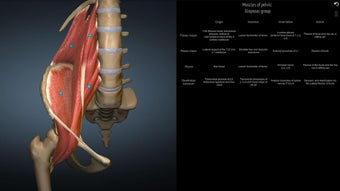

Anatomy Learning - 3D Atlas è un'app gratuita per Android che appartiene alla categoria Medicina ed è stata sviluppata da AnatomyLearning. È consigliata per principianti, studenti di medicina, apprendisti visivi, professionisti medici, medici.

Questa app è meglio conosciuta per le seguenti caratteristiche e qualità: strumento di studio, apprendimento dell'anatomia, strumento di apprendimento e riferimento di base.

La gente dice sono a scuola per radiografia e sono un apprendista piuttosto visivo, bella app per principianti, incantevole per gli appassionati di fitness.